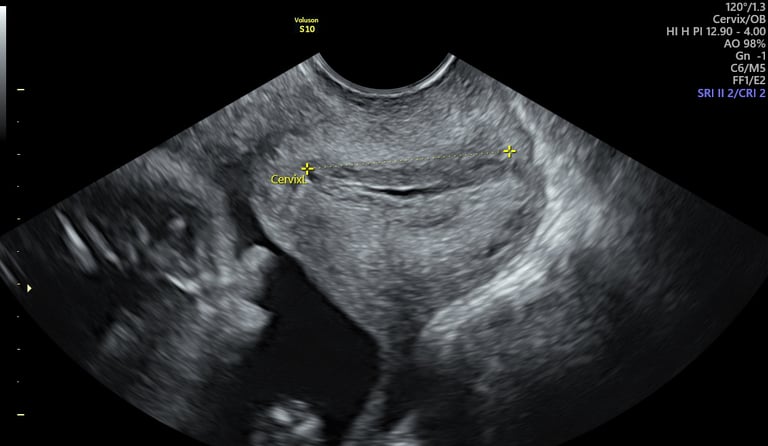

cervicometría